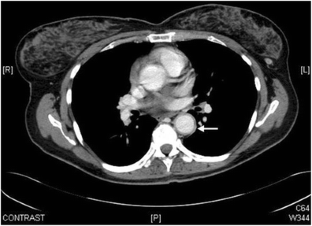

Fig. 2